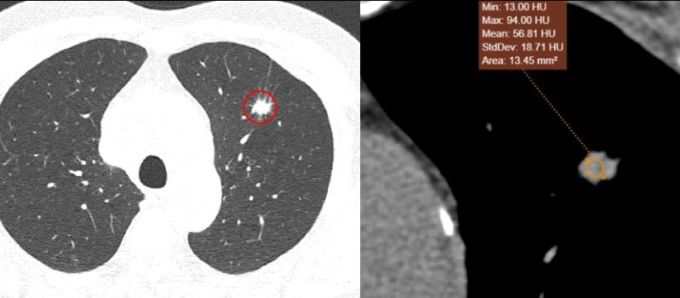

El paciente había fumado durante los últimos 20 años, con un promedio de dos paquetes al día. Una tomografía computarizada realizada en el Hospital General Medlatec reveló un nódulo de 12 x 13 mm en el lóbulo superior del pulmón izquierdo, con constricción del parénquima pulmonar circundante. Además, se observaron numerosos ganglios linfáticos grandes alrededor del mediastino y una masa anormal en la glándula suprarrenal izquierda de 3,7 x 4,3 cm.

La tomografía computarizada muestra una masa (mancha blanca rodeada de un círculo rojo) en el lóbulo superior izquierdo del pulmón del paciente. Foto: Proporcionada por el hospital.